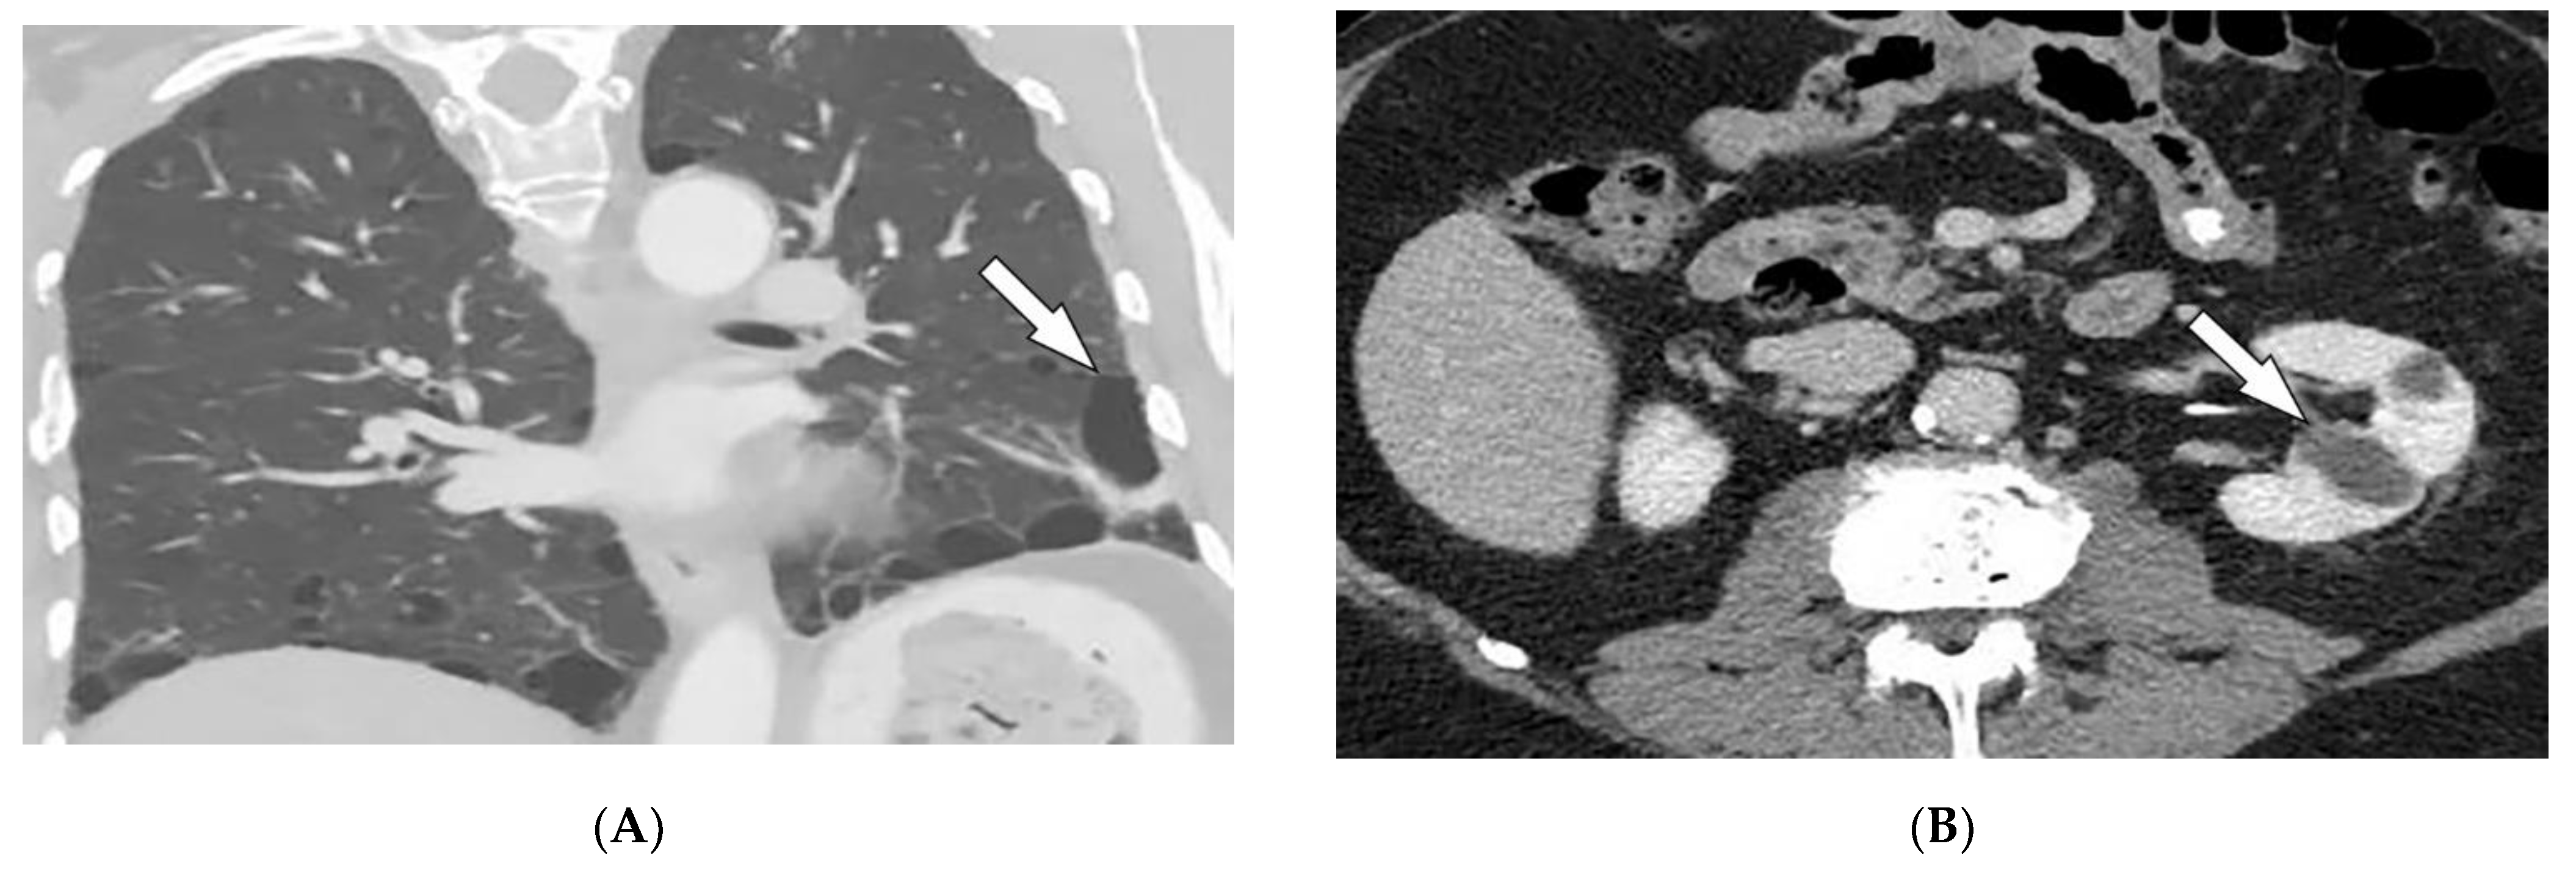

3.7. Birt–Hogg–Dube’ Syndrome

| Birt–Hogg–Dube syndrome | Fibrofolliculomas, trichodiscomas, acrochordons Lung cysts (pneumothorax) Renal cysts | Bilateral basilar predominant, thin-walled cysts abutting pleura and pulmonary vessels |